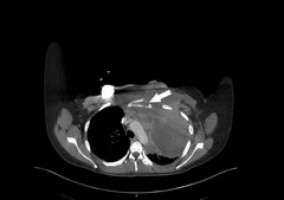

“We hypothesised that distant metastases are rare in head and neck cancer. Since the lungs are the most common site of metastases, we wanted to evaluate if a chest CT scan would be just as effective PET/CT scans for some patients,” said Jeffrey Liu, MD, FACS, an attending surgeon at Fox Chase who specialises in otolaryngology.

The findings suggest that while PET/CT scans offer many advantages for initial evaluation of this disease, for example showing metabolic functional data to aid in the evaluation of any masses, given the pattern and frequency of DM in head and neck cancer, a CT chest scan may be just as effective for evaluation of DM.